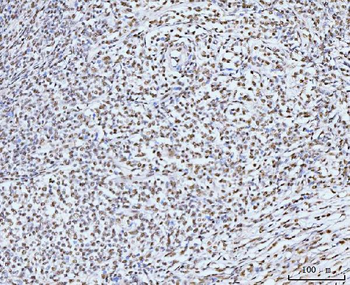

100 μl, 50 μl, 200 μl - HSC70 Mouse Monoclonal Antibody [orb704174]Featured

IF, IHC-Fr, IHC-P, WB

Human, Mouse, Rat

Mouse, Rat

Mouse

Monoclonal

Unconjugated

100 μl, 50 μl, 200 μl - ATF4 Recombinant Rabbit Monoclonal Antibody [orb704304]Featured